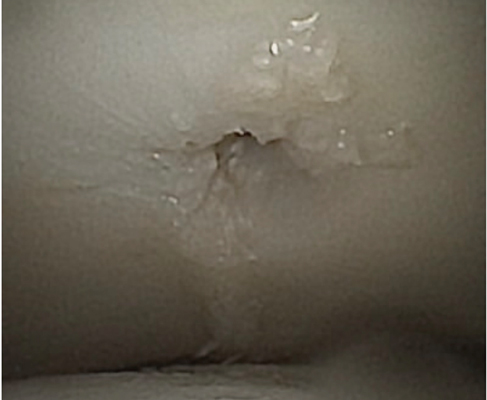

TOTAL ANKLE REPLACEMENT :: ORIF CALCANEUS :: ORIF ANKLE FRACTURE DISLOCATION :: COMPLEX BUNION AND LESSER TOE CORRECTION :: TALUS FRACTURE -1 :: TALUS FRACTURE -2 :: LISFRANC REPAIR :: COMPLEX TRIPLE ARTHRODESIS 1 :: COMPLEX TRIPLE ARTHRODESIS 2 :: MINIMALLY INVASIVE BUNION REPAIR 1 :: MINIMALLY INVASIVE BUNION REPAIR 2 :: ARTHROSCOPIC CARTILAGE REPAIR :: TENEX SPUR DEBRIDEMENT :: Haglunds Debridement and Achilles Repair